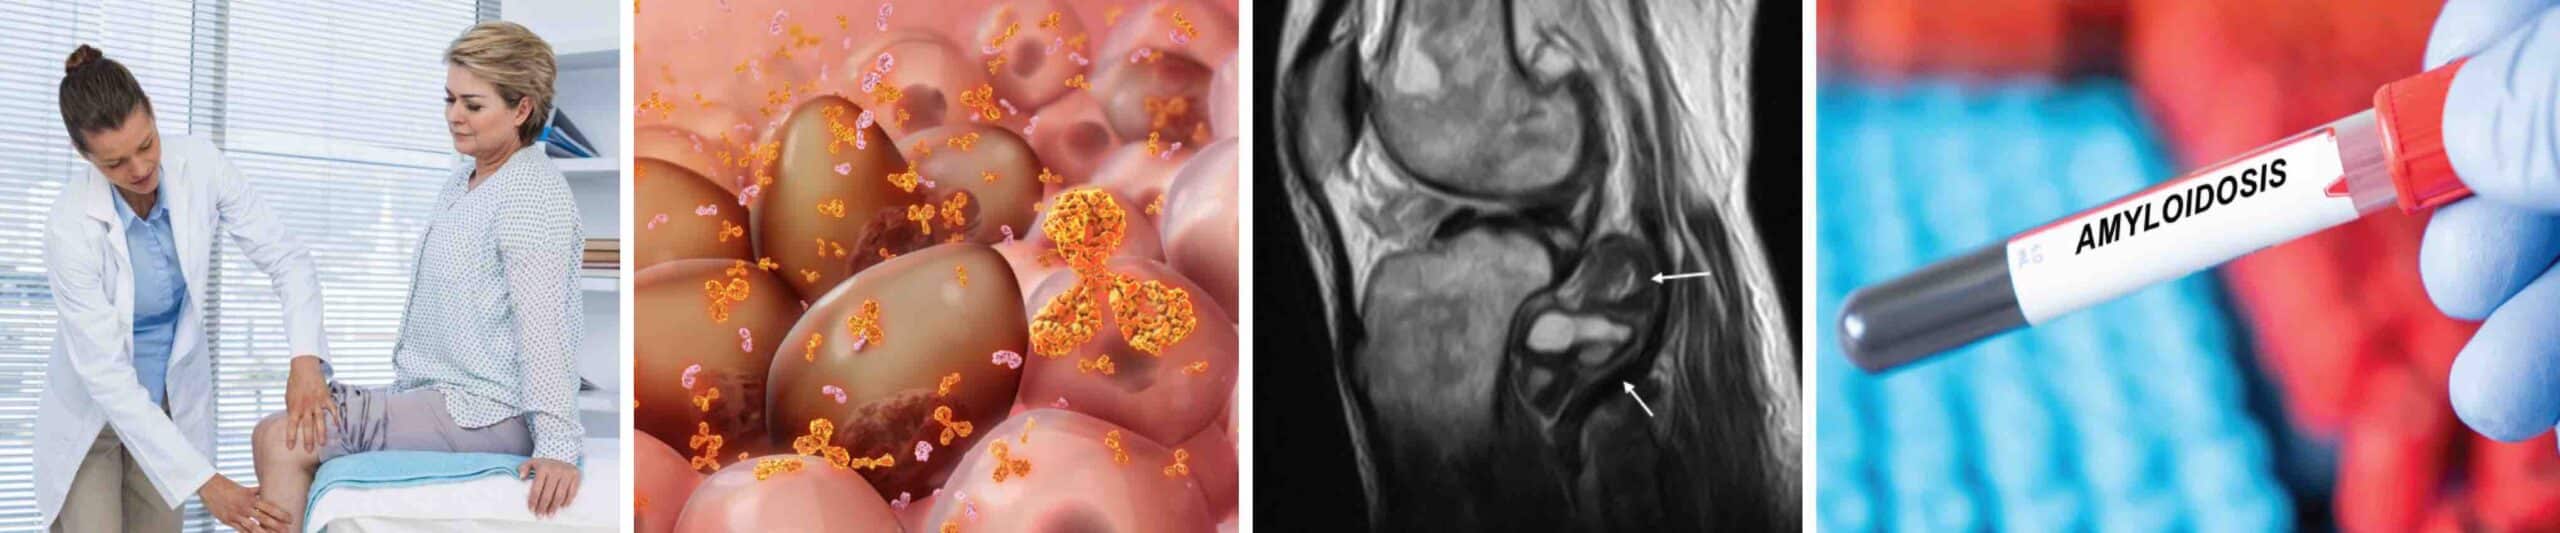

DOR NO JOELHO E AMILOIDOSE

Dor no joelho pode ser um dos sintomas da amiloidose. A amiloidose é uma doença rara caracterizada pelo acúmulo anormal de proteínas chamadas amiloides nos tecidos e órgãos do corpo. Essas proteínas, ao se depositarem de forma inadequada, comprometem o funcionamento normal dos órgãos afetados, como rins, coração, fígado, nervos periféricos e articulações. Amiloides são proteínas anormais que sofreram um dobramento incorreto e se acumulam no organismo na forma de fibras insolúveis. As proteínas normalmente têm uma estrutura tridimensional específica, chamada de dobramento, que determina a sua função. Quando uma proteína se dobra de maneira errada e não é degradada pelo organismo, ela pode formar fibras rígidas e pegajosas, chamadas de fibras amiloides. Essas fibras, que não são solúveis, tendem a se acumular nos espaços entre as células, formando depósitos. Existem vários tipos de amiloidose, dentre os quais três são os mais comuns: amiloidose AL ( primária ), amiloidose AA ( secundária ) e amiloidose por transtirretina ( ATTR ). Em alguns casos a amiloidose pode se manifestar nas articulações, especialmente nos joelhos, levando ao que é chamado de artropatia por amiloide.

Artropatia por amiloide no joelho acontece quando há acúmulo de depósitos de proteínas amiloides dentro da articulação do joelho, levando a inflamação, dor, inchaço e limitação dos movimentos, sintomas semelhantes a outras doenças articulares mais comuns como a artrose e a artrite reumatóide. As proteínas amiloides no joelho se depositam na membrana sinovial, cartilagem e tecidos periarticulares. Esses depósitos de amiloides tornam a articulação do joelho mais espessa e rígida, podem desgastar a cartilagem e provocam dor persistente e inchaço, mesmo sem sinais claros de inflamação intensa. Dor crônica ou intermitente, inchaço, rigidez articular, diminuição da mobilidade e até a sensação de bloqueio da articulação são os sintomas mais comuns da amiloidose no joelho.

O diagnóstico da amiloidose no joelho é feito pala história clínica completa do paciente, exame físico do joelho afetado e por exames complementares. Os exames mais importantes são: ressonância magnética do joelho, análise do líquido sinovial, biópsia sinovial ou de outros tecidos articulares afetados, eletroforese de proteínas e imunofixação. Um corante especial, chamado de vermelho do Congo, é usado para identificar amiloides ao microscópio. O diagnóstico precoce da doença é importante para evitar complicações graves, como a falência de órgãos ou limitações funcionais permanentes.